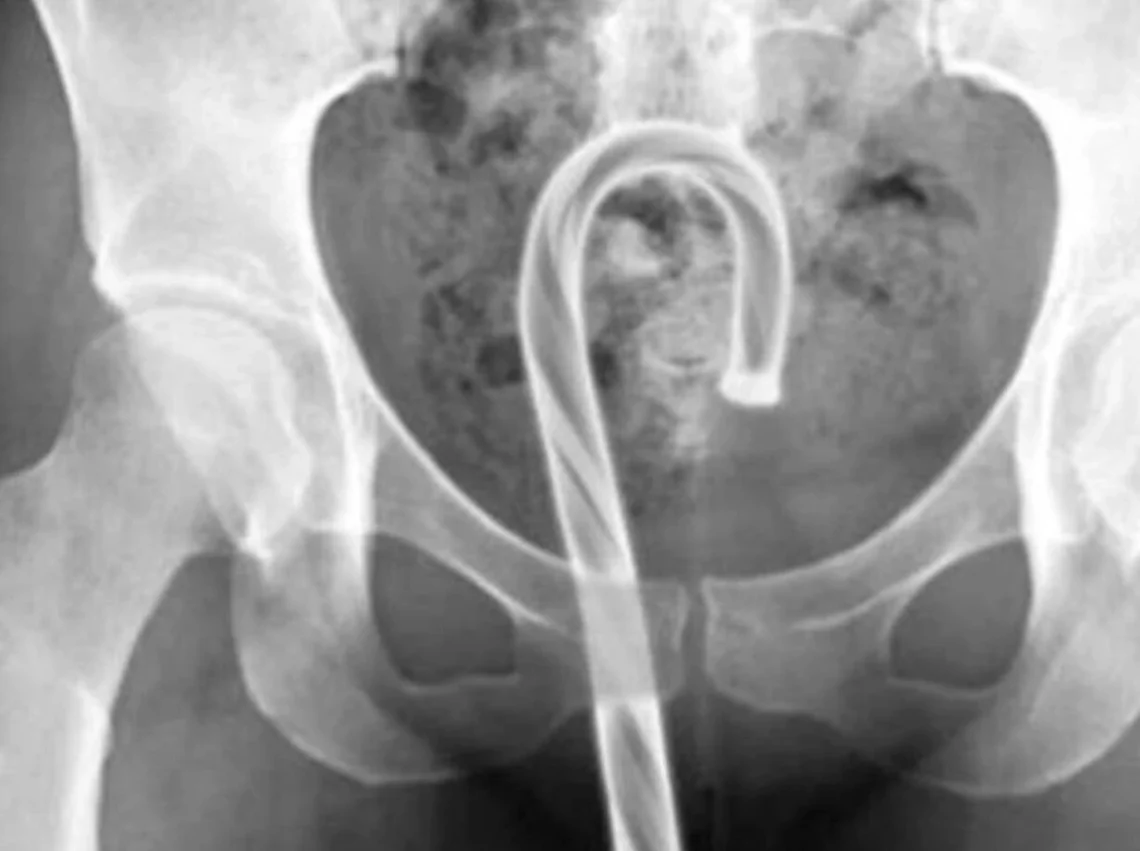

É considerada assustadora a quantidade de casos registrados todos os anos em prontos-socorros envolvendo pessoas que precisaram de atendimento médico após introduzir objetos nos órgãos genitais. Seja por curiosidade, práticas sexuais de risco ou fetiches, o hábito pode provocar lesões graves, infecções, perfurações internas e até risco de morte, segundo especialistas em saúde.

Levantamento do site americano Defector, com base nos dados mais recentes de 2024 da Comissão de Segurança de Produtos de Consumo dos Estados Unidos, revela um número alarmante de atendimentos emergenciais relacionados a objetos presos na vagina, no pênis e no ânus. A maioria dos casos exige intervenção médica.

Médicos alertam que a introdução de objetos inadequados pode causar sangramentos, infecções severas, necrose, perfuração de órgãos e danos permanentes à função sexual. Em muitos casos, a retirada exige cirurgia.